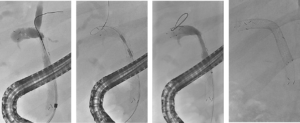

Een 68-jarige vrouw werd verwezen in verband met verdenking op een perihilair cholangiocarcinoom, Bismuth type IIIb (figuur 1). In verband met icterus en mogelijke hemihepatectomie links werd er een plastic endoprothese in de rechter ductus hepaticus geplaatst. De galwegen links werden bewust niet gecontrasteerd. Tevens werd een brush afgenomen die de diagnose adenocarcinoom bevestigde. Vanwege snel toegenomen vaatbetrokkenheid kwam patiënte niet meer in aanmerking voor resectie of levertransplantatie. Derhalve werd gestart met palliatieve systeemtherapie en werd de plastic stent electief gewisseld voor een ‘uncovered’ metalen stent (uSEMS). Aangezien er, op basis van het lage bilirubinegehalte (11 μmol/L), reeds voldoende drainage met een unilaterale stent was bereikt, werd er niet aanvullend bilateraal gedraineerd. In studieverband (RACCOON-pilot [NL9144]) werd de stenose geableerd met endobiliaire radiofrequente ablatie (eRFA), met het doel om de duur van de stentdoorgankelijkheid te verlengen. Met een 22 mm ELRA-electrode (Taewoong Medical) werd de stenose 90 seconde geableerd met 7 watt en target temperatuur van 75 graden (figuur 2). De ductus cysticus werd niet in het traject betrokken om een post-procedurele cholecystitis te voorkomen. Na verwijderen van necrotisch materiaal met een extractieballon werd een 80 x 8 mm uSEMS geplaatst (figuur 3). 5 maanden later ontwikkelde patiënte klachten passend bij stentobstructie. Er werd opnieuw eRFA verricht van de stenose in de stent en een tweede 60 x 8 mm uSEMS in de reeds aanwezige stent geplaatst (figuur 4). Weer 5 maanden later ontwikkelde patiënte recidiverende klachten. Er werd opnieuw eRFA verricht, maar ditmaal werd geen aanvullende stent geplaatst (figuur 5). Patiënte overleed 5 maanden later zonder terugkerende obstructie, 2 jaar na de diagnose.